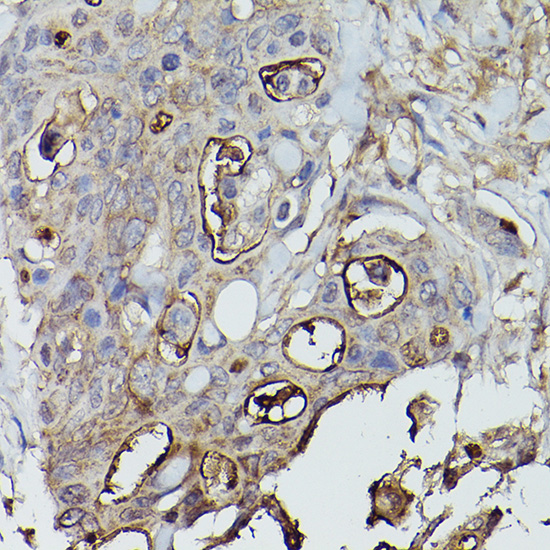

Immunohistochemistry of paraffin-embedded human colon carcinoma using Alkaline Phosphatase (ALPL) Rabbit pAb.

Immunohistochemistry of paraffin-embedded human lung cancer using Alkaline Phosphatase (ALPL) Rabbit pAb.

IHC 1:50 - 1:200